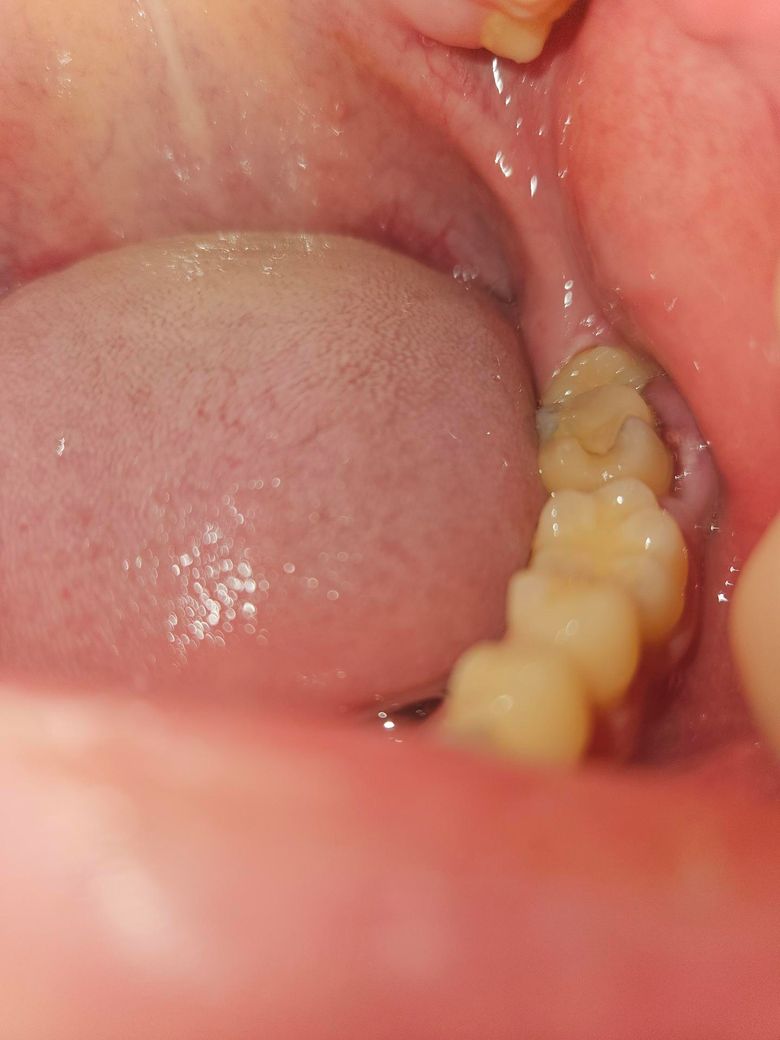

4일전에 아프기 시작해서 덱시부프로펜 먹으면서 참다가 더이상은 안될 것 같아서 안쪽을 찍어보니 저렇게 부어있습니다. 인터넷 보면 재신경치료나 무슨 절제술 해야한다는데 그렇게 심각한가요?

사진으로 봤을 경우에 잇몸은 손상된 상태에서 감염이 된것으로 보입니다. 감염의 원인을 제거하고 잇몸에 가해지는 자극을 줄여주는 것이 좋습니다.

치아 옆부분이 깨지면서 잇몸이 많이 부은 상태 같습니다. 치과에 가셔서 잇몸을 잘라내고 크라운 치료를 하시는게 좋을것같습니다.

잇몸관련 문제일지 아니면 주변 어금니 문제일지 아니면 사랑니로 인한 치관주위염인지는 검사해봐야 알 수 있고 각기 원인에 따라 치료방법이 다릅니다